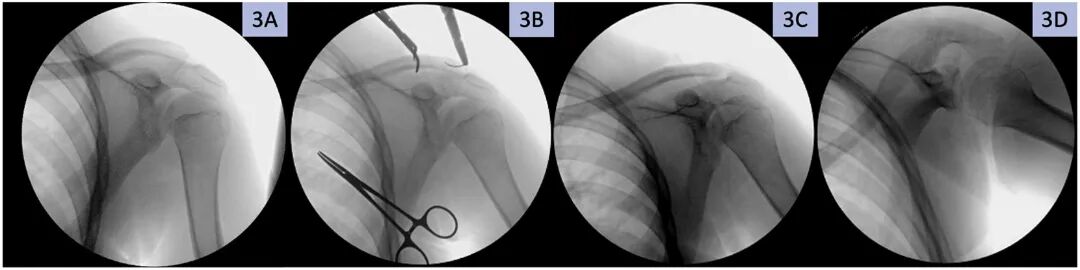

图3。左锁骨远端远端骨折的缝合固定术中前后位透视图,显示A)切口前的术前图像,B)缝合线通道,以及C)前后位和D)腋窝复位视图。

在骨折端的提取和锐器清创后,使用骨膜提升器和Freer提升器将内侧骨干固定到外侧骨折块上。一个尖头复位钳保持初步固定。骨折键入,并通过双平面透视确认减少。使用2毫米克氏针在骨折部位内侧约1.5厘米处(1个前部和1个后部)形成2个上孔。对外侧片段重复此步骤,并注意避免侵犯肩锁关节。

两条2号FiberWire缝合线(Arthrex,Naples,FL,USA)通过这些孔穿过骨折部位,形成8字形结构,并通过透视确认(图3 )。术中复位图像如图4所示。该地点被灌溉,然后分层关闭。